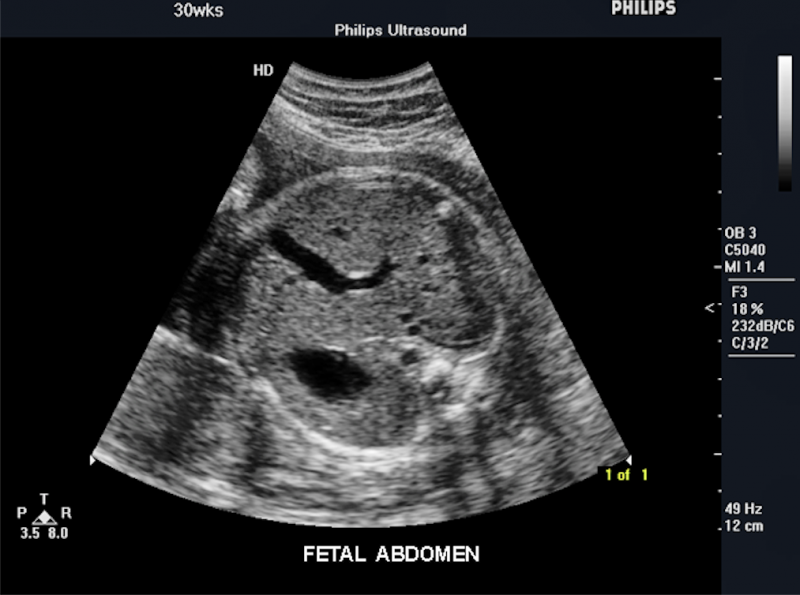

Below is a collection of prenatal ultrasound pictures from the Imaging Technology News (ITN) archive. Use the arrows to click through the image gallery. It includes transvaginal ultrasound images and fetal echocardiogram images. Fetal imaging is referred to by many names, including pregnancy sonograms, pregnancy ultrasound, endovaginal ultrasound, obstetric ultrasound, OB ultrasound, baby ultrasound, prenatal ultrasound. Fetal heart ultrasound is also called baby echo or prenatal echo.